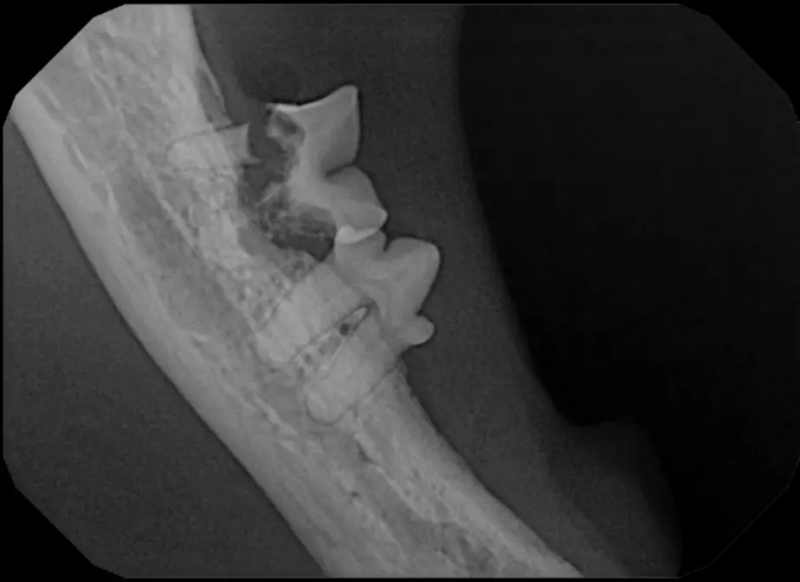

Tooth Resorption

Tooth resorption is a disease process where the body begins to break down the adult tooth. It is widely known to occur in cats but can also occur in dogs. In cats these lesions are thought to be inflammatory, while in dogs they can be more of a replacement resorption process. These lesions can be very painful and should be treated, generally with extraction depending on the type of resorption that is occurring. The disease can be progressive and affect many teeth over several years. It is important to have regular checkups and yearly dental cleanings to monitor for these lesions.